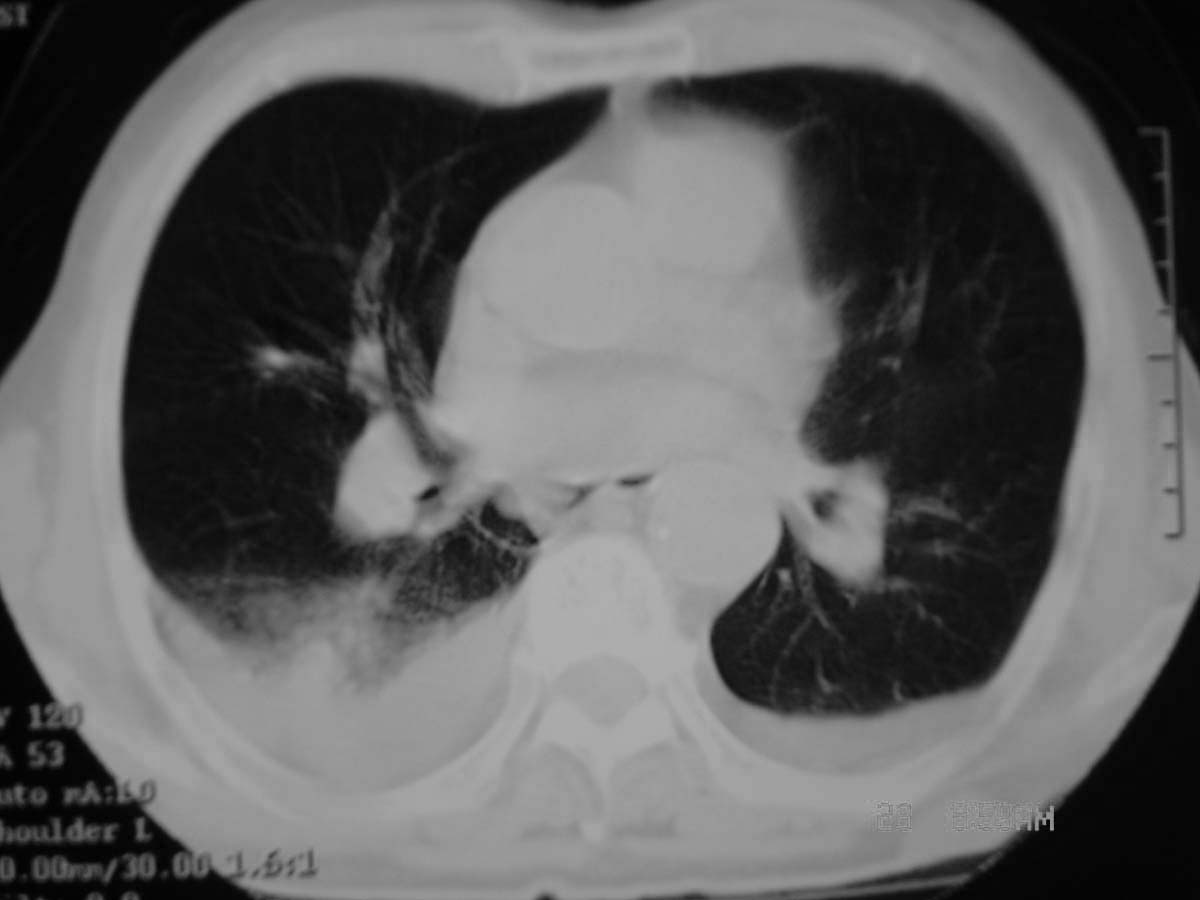

以下是引用守望可可西里在2006-11-23 14:33:00的发言:[br][br] 糖尿病病人很容易继发结核,病人又有双侧胸膜增厚、粘连、胸腔积液以及双上肺的斑片状、条索状影结核病灶影,以一元论考虑,右下肺病变首先考虑干酪性肺炎,可以正规抗炎治疗后复查,排除一般的肺炎。